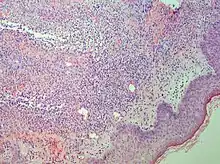

Interface dermatitis with lichenoid inflammation

| Generally/Not otherwise specified | Typical findings:[2]

|

| Lichen planus | Irregular epidermal hyperplasia with a jagged “sawtooth” appearance, compact hyperkeratosis or orthokeratosis, foci of wedge-shaped hypergranulosis, basilar vacuolar degeneration, slight spongiosis in the spinous layer, and squamatization. The dermal papillae between the elongated rete ridges are frequently dome shaped. Necrotic keratinocytes can be observed in the basal layer of the epidermis and at the dermal-epidermal junction. Eosinophilic remnants of anucleate apoptotic basal cells may also be found in the dermis and are referred to as “colloid or civatte bodies”. Whickham striae are usually seen in the areas of hypergranulosis. Vacuolar degeneration at the basal layer may be noted leading to focal subepidermal clefts (Max Joseph spaces). Squamatization occurs as a result of maturation and flattening of cells in the basal layer. It happens in areas of marked hypergranulosis with prominence of the sawtooth pattern of rete ridges. Wedge-shaped hypergranulosis can occur in the eccrine ducts (acrosyringia) or hair follicles (acrotrichia). In the hypertrophic subtype, the associated hyperkeratosis, parakeratosis, hypergranulosis, papillomatosis, acanthosis, and hyperplasia markedly increased with thicker collagen bundles forming in the dermis. Moreover, the rete ridges are more elongated and rounded as opposed to the typical sawtooth pattern. In atrophic LP, loss of the rete ridges and dermal fibrosis is prominent. In vesiculobullous LP, the disease progression is quicker. Hence, some of the distinctive features such as hyperkeratosis, hypergranulosis, or dense lymphocytic dermal-epidermal infiltrate may not be present. LP lesion may resolve with residual hyperpigmentation caused by a persistent increase in the number of melanophages in the papillary dermis.[9] | ![]() | ![]() |